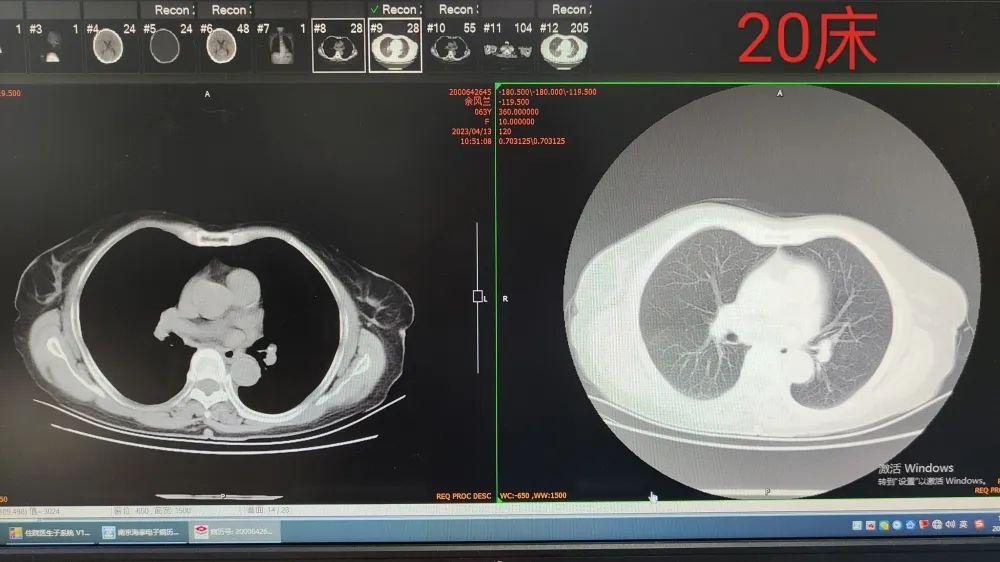

現(xiàn)在20床的患者小余是為李教授專程而來(lái)。8個(gè)多月前他在上海市肺科醫(yī)院確診了肺腺癌,現(xiàn)一直行靶向治療,如今病灶較前明顯縮小,家屬有行手術(shù)治療的傾向,但由于初診時(shí)懷疑縱隔及雙肺門(mén)淋巴結(jié)轉(zhuǎn)移可能,腫瘤臨床分期已達(dá)IV期,我院腫瘤科參考患者初診時(shí)的資料即否定了手術(shù)的治療方案,考慮給患者行局部的射頻消融治療。李教授了解病史后表示,患者初診的基線資料非常重要,靶向治療8月后左下肺及肺門(mén)的腫塊都有縮小,也能反證當(dāng)初對(duì)腫瘤轉(zhuǎn)移情況的判斷,雙肺門(mén)淋巴結(jié)為轉(zhuǎn)移灶。如此一來(lái),臨床分期為IV期的患者,李教授也表示手術(shù)不會(huì)作為優(yōu)選,肯定了我院提出的局部射頻消融的治療方案。